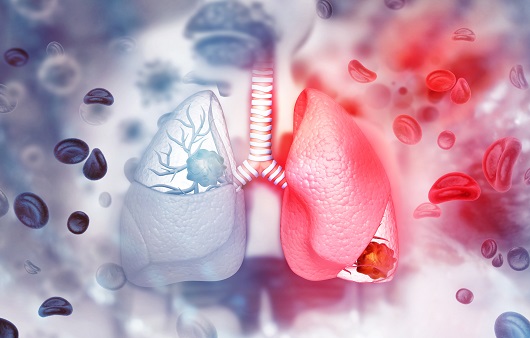

폐암은 원발성 폐암을 말하며 원발성 폐암은 폐에서 기원하는 악성 종양을 말한다. 폐로 전이된 암은 폐로 전이된 것으로 분류되며, 폐암이라기 보다는 기원 장기로 전이된 것으로 분류된다. 폐암은 조직학적 유형에 따라 크게 소세포폐암과 비소세포폐암으로 분류된다.

둘째, 환경적 요인이 '폐암'으로 이어질 수 있습니다. 일상 생활에서 흡입되는 발암 물질은 폐암을 유발할 수 있습니다. 즉, 대기오염 가스 중의 발암물질을 흡입하거나 흡연을 통한 발암물질을 직간접적으로 흡입함으로써 폐암이 발생할 수 있습니다. 흡연은 폐에 매우 치명적이어서 흡연은 폐암의 가장 큰 원인이며, 비흡연자도 간접흡연으로 폐암에 걸릴 수 있습니다.

이러한 폐암의 원인으로 인해 폐암으로 진단되기 전에 폐암 초기증상을 조기에 발견하면 다른 장기로의 전이나 진행성 폐암으로의 진행을 어느 정도 지연시키거나 적절하게 치료할 수 있지만 일반적으로 폐암의 초기 단계는 특별한 징후나 증상이 없으므로 조기에 발견하는 경우는 극히 드뭅니다.